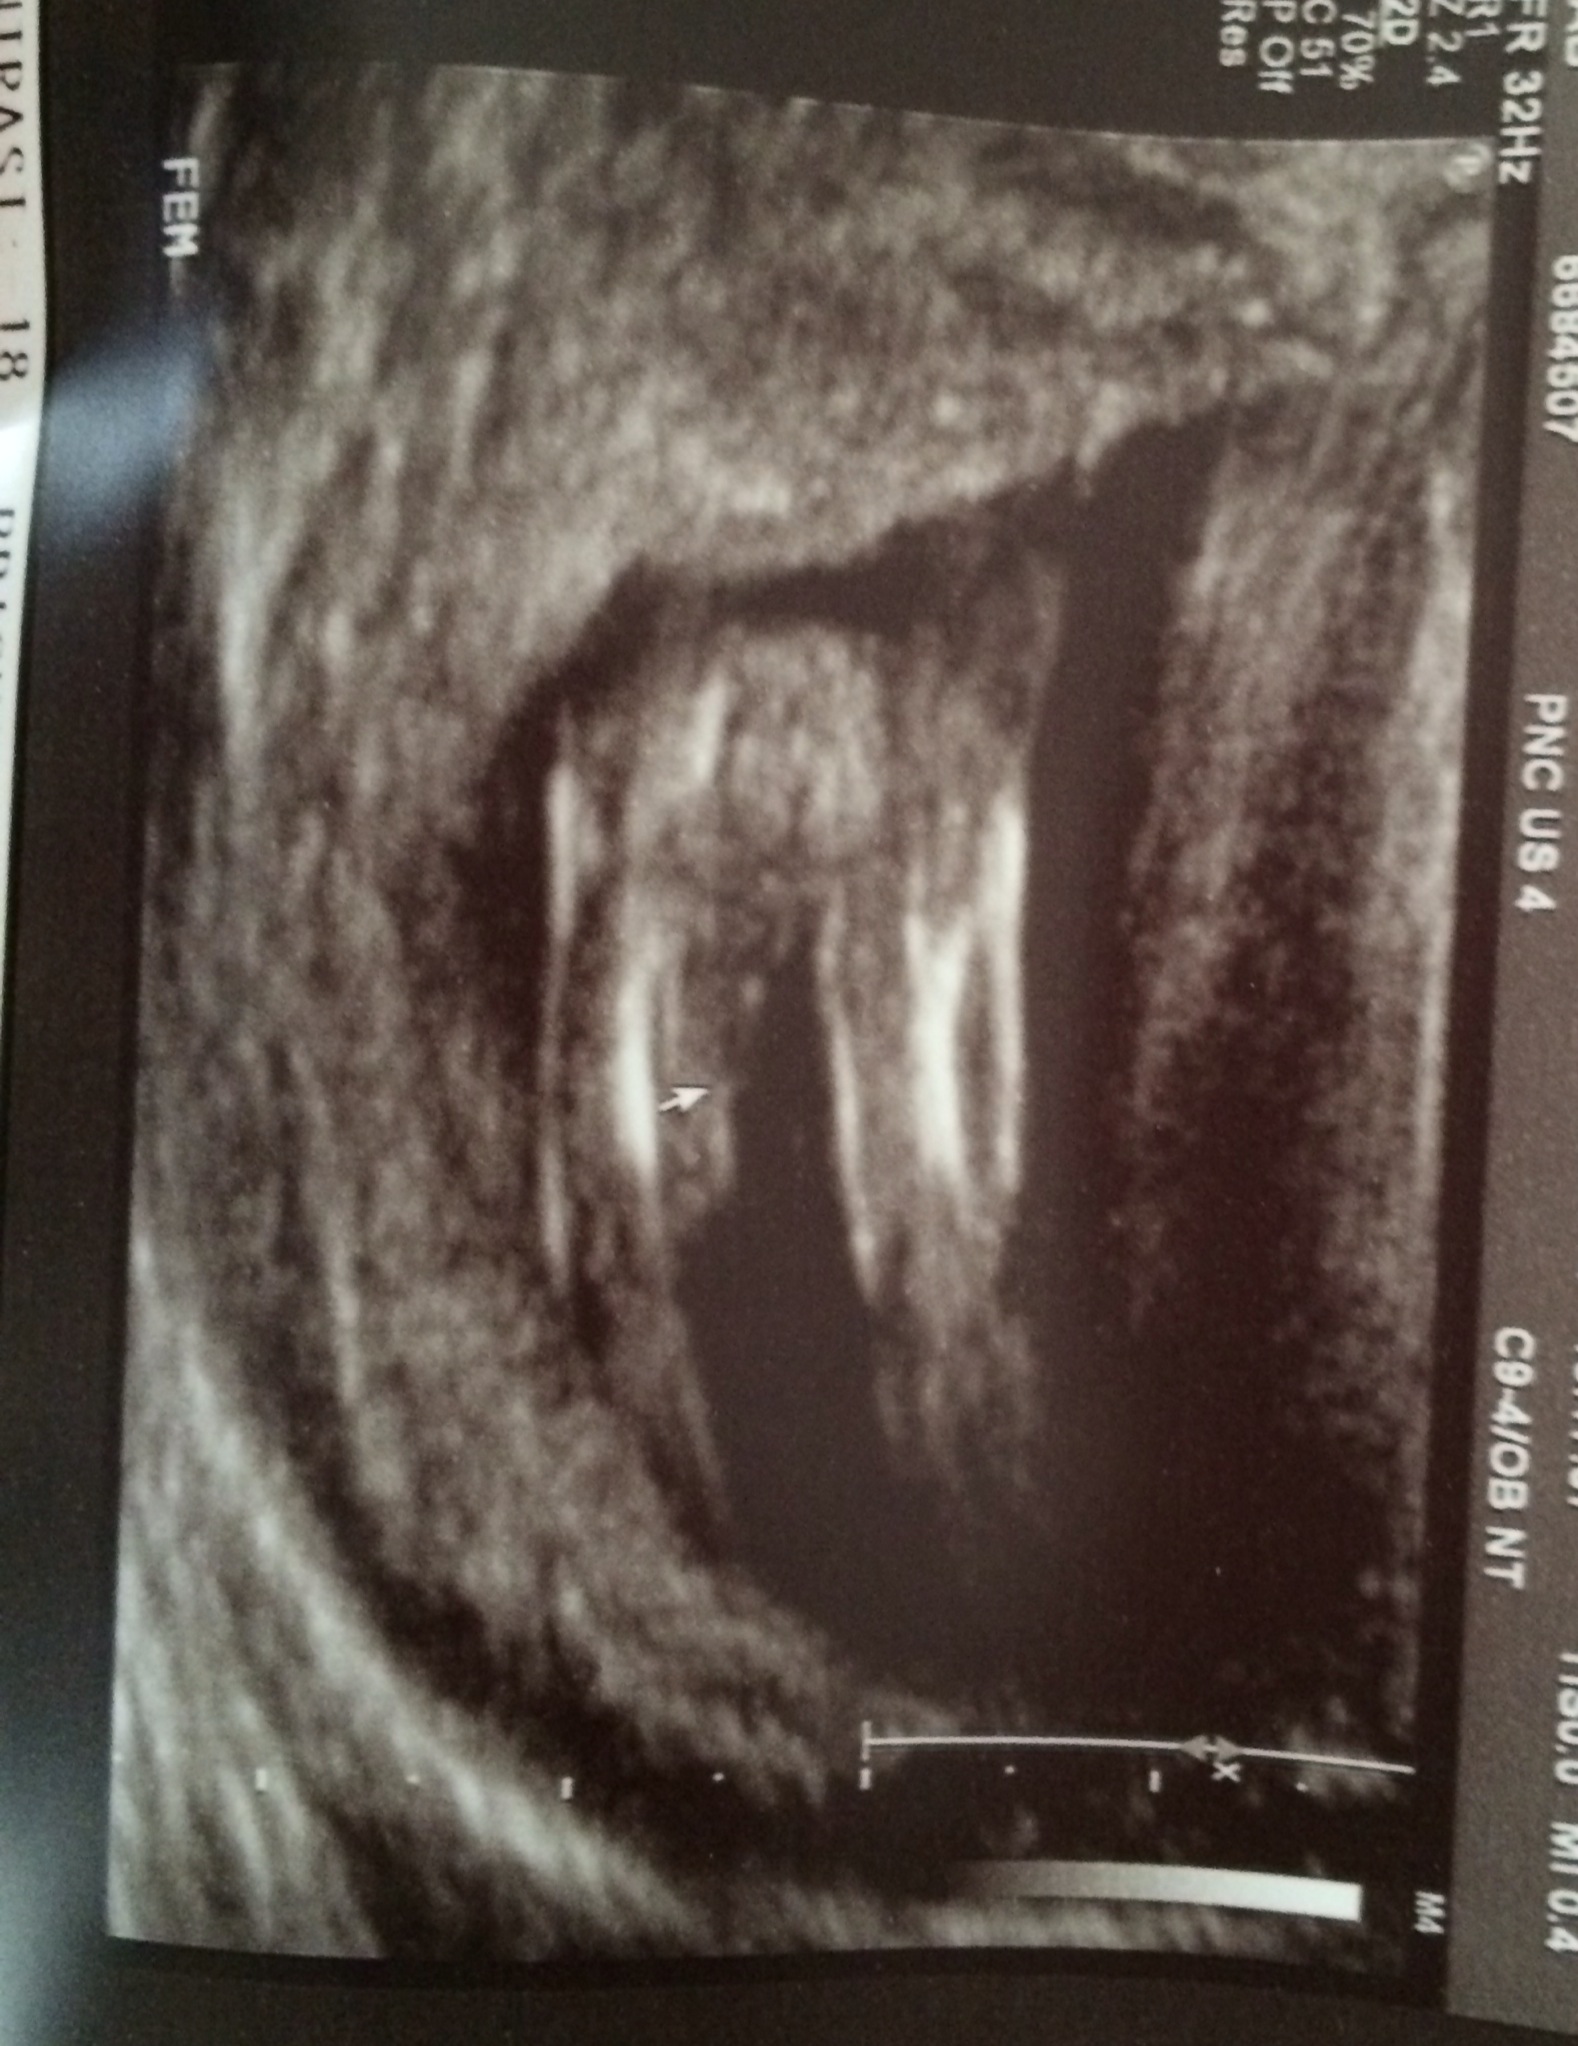

Can anyone tell what this baby's gender is? This is a 12.5 wk ultrasound picture.

Maybe a boy

Profile shot? Otherwise it is too early but somehow this still looks boyish to me!

Looks like a boy x

I would guess boy

I am guessing boy also